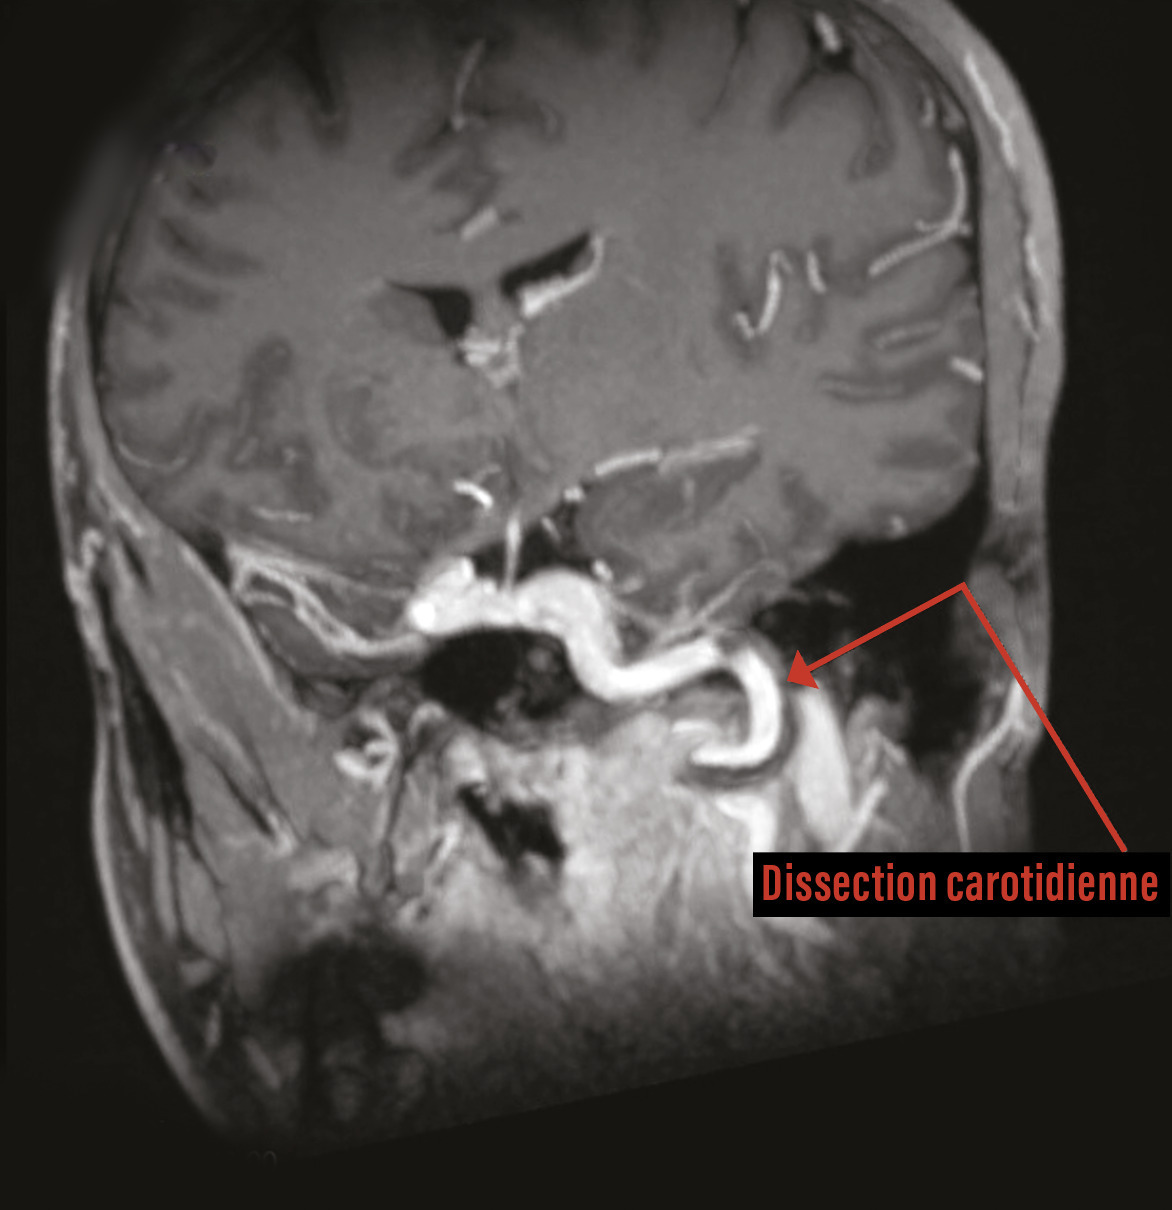

Un homme de 45 ans consulte en raison de l’apparition de céphalées inhabituelles accompagnées d’un ptosis et d’un myosis de l’œil gauche. Il rapporte un rétrécissement du champ visuel et des phosphènes apparus depuis deux jours, faisant suite à l’apparition progressive de céphalées hémicrâniennes gauches insomniantes, ainsi qu’une anesthésie des quatrième et cinquième doigts de main gauche (en lien avec un syndrome du canal carpien connu). Cliniquement, le patient n’a aucun déficit neurologique. Hormis une hypertension artérielle et le fait d’être un homme, il n’a aucun facteur de risque cardiovasculaire connu. Une angio-imagerie par résonance magnétique (aIRM) est réalisée en urgence devant ce syndrome de Claude-Bernard-Horner partiel et révèle une dissection de l’artère carotide interne gauche sur 3 cm (fig. 1 et 2) .

Le syndrome de Claude-Bernard-Horner (SCBH) est caractérisé par la concomitance de quatre signes cliniques : ptosis, myosis, pseudo-énophtalmie, ainsi qu’une vasodilatation et une absence de sudation localisée (anhydrose).1 Il est dû à l’atteinte des fibres du système nerveux sympathique innervant l’œil et/ou l’orbite. Face à un syndrome de Claude-Bernard-Horner, il faut envisager cinq causes : l’accident vasculaire cérébral (notamment le syndrome de Wallenberg), le syndrome de Pancoast-Tobias, l’algie vasculaire de la face, une tumeur cérébrale (surtout chez l’enfant) et enfin la dissection de la carotide interne. Plus de la moitié des cas de dissection aortique sont spontanés, sans traumatisme préalable identifié. La recherche d’une dissection vasculaire chez un patient présentant une lésion cervicale traumatique doit être systématique.

Dans ce cas, la cause étant une dissection de l’artère carotide interne gauche (artère intracrânienne), la prise en charge inclut, selon les recommandations, la surveillance neurologique, la prévention des agressions cérébrales secondaires d’origine systémique (ACSOS) ainsi que l’administration d’un antiagrégant plaquettaire (aspirine en aigu) et au long cours (utilisation possible d’une anticoagulation) en prévention secondaire jusqu’à régression des lésions à l’imagerie.2,3